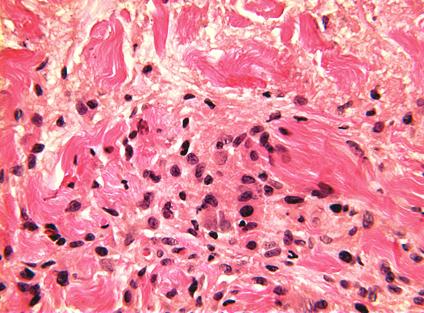

栅栏样模式:特征为真皮中上层淋巴组织细胞炎性浸润,而炎性浸润呈栅栏样包绕胶原及弹性蛋白变性区域。胶原变性区域表现为嗜酸性纤维物质被嗜碱性黏蛋白沉积物所分隔。也可能存在嗜酸性粒细胞。

图:右侧为坏死中心,边缘见淋巴细胞和组织细胞,左侧为多核巨细胞(HE 400x).